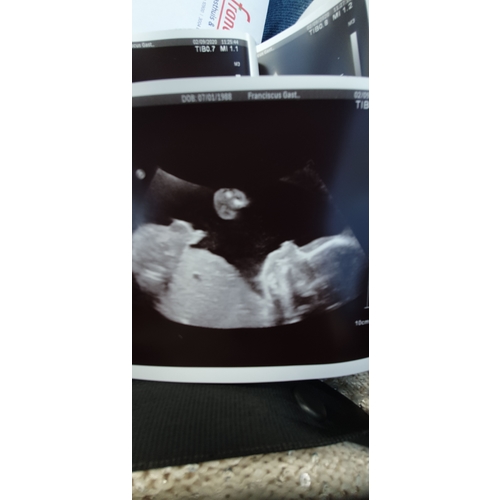

Wat grappig! Door zulke topics durf ik nog niks te kopen haha hier zeiden ze een jongetje wie weet hoor ik dinsdag dat t toch een meisje wordt 🙃

Jazeker! Laat je het ook weten spannend .. nee ik had ook geen geslachtsbepaling echo hoor maar ik moest naar het ziekenhuis voor een medische echo toen vroeg de echopiste of wij geslacht al wouden weten omdat t heel goed zichtbaar was volgens haar was geen twijfel mogelijk is een jongen 🙊